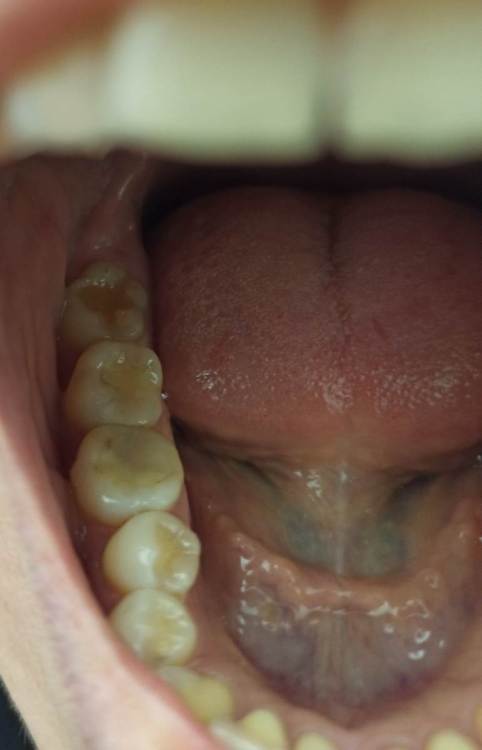

Котенька Опубликовано 10 июня, 2023 Автор Поделиться Опубликовано 10 июня, 2023 Прилагаю фото,вдруг будет более информативно. На фото с правой стороны все зубы мудрости есть,сверху кариес.На левой стороне нет. Ссылка на комментарий

Irouil Опубликовано 10 июня, 2023 Поделиться Опубликовано 10 июня, 2023 Не слышал никогда сколько нибудь вразумительных доводов о пользе симметрии в зубных рядах. На фото видно не все, но с большой долей вероятности я бы не стал рекомендовать удалять эти зубы мудрости Я полагаю что стоит ожидать улучшения ситуации слева в ближайшем будущем, Возможно причина дискомфорта в слизистой связана с чем-то другим, тут надо осматривать очно. Лечить кариес, конечно, нужно. Ссылка на комментарий